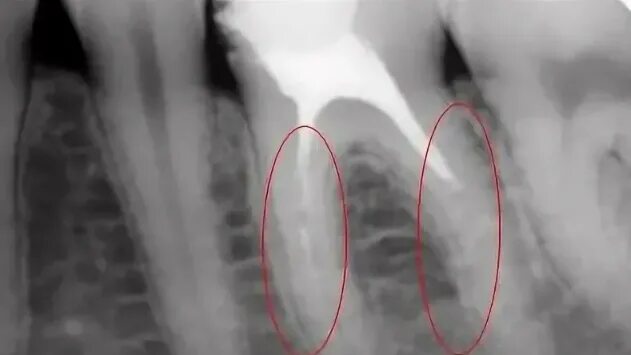

Воспаление зуба после удаления нерва